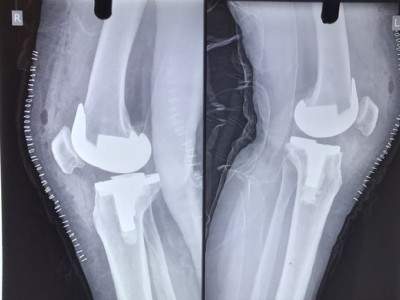

Patient Photos

POST-OPERATIVE